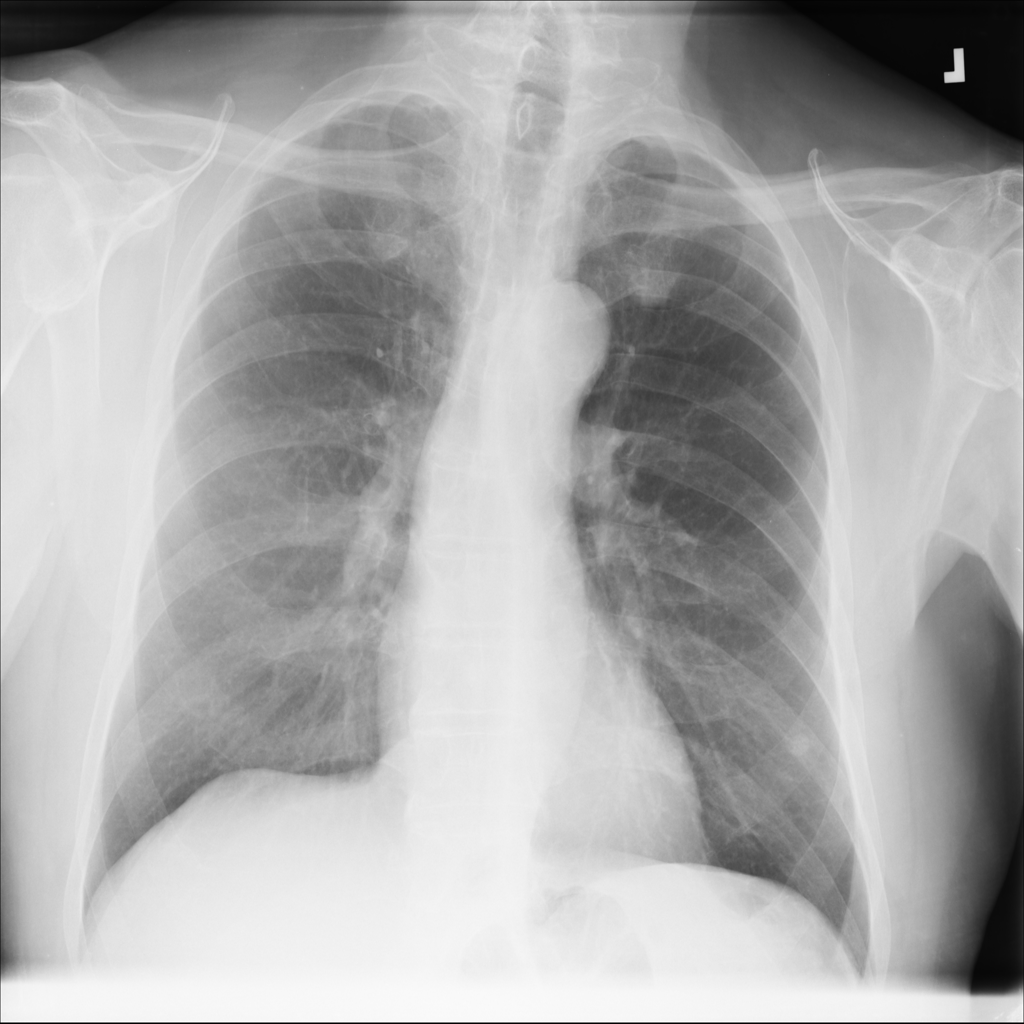

Nodule

A nodule is a small rounded opacity in the lung or chest field. It is a descriptive imaging finding that can be benign or more concerning depending on size, appearance, and context.

Showing up to 90 reference images for Nodule.

PAT-F3E7 · IMG-002Nodule

PAT-F3E7 · IMG-002

PA